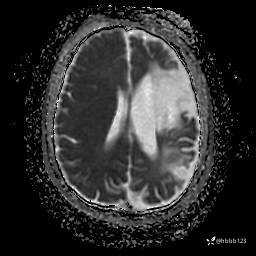

T2 Flair: